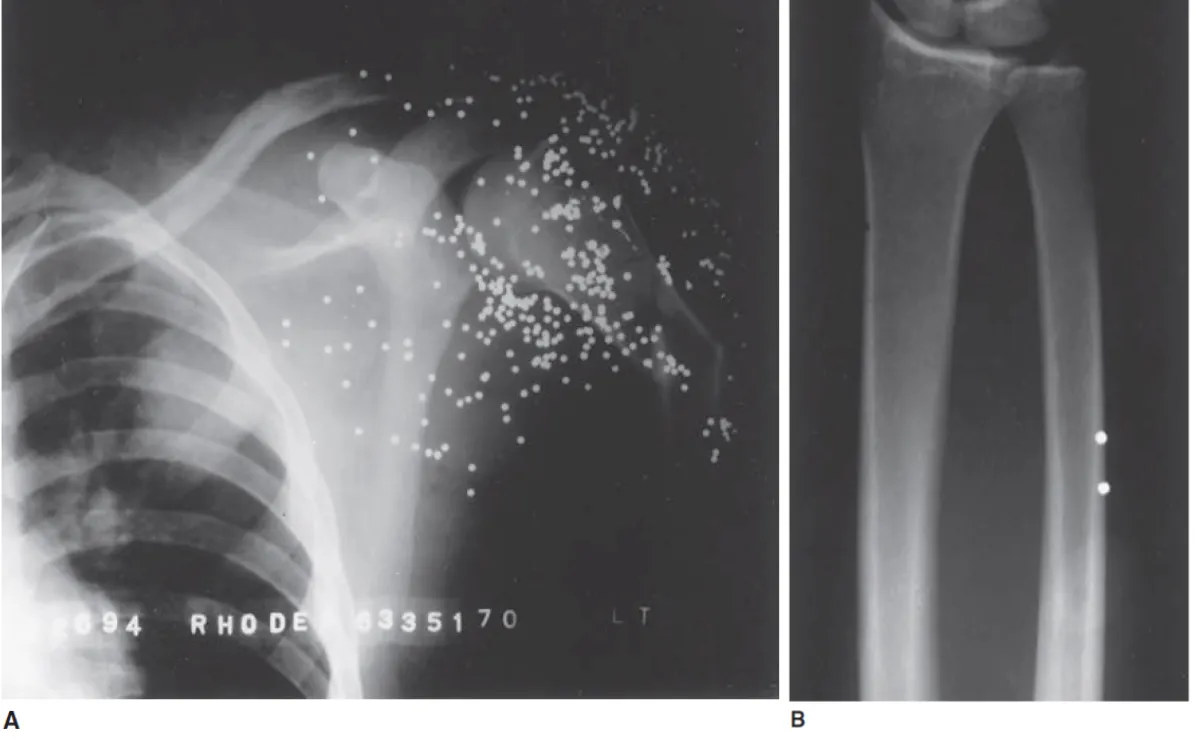

*그림 은 산탄총에 의한 를 나타내며 뼈 * 226-3 injury 226-3 injury soft tissue, 등의 구조에 총탄이 잔류할 수 있음.